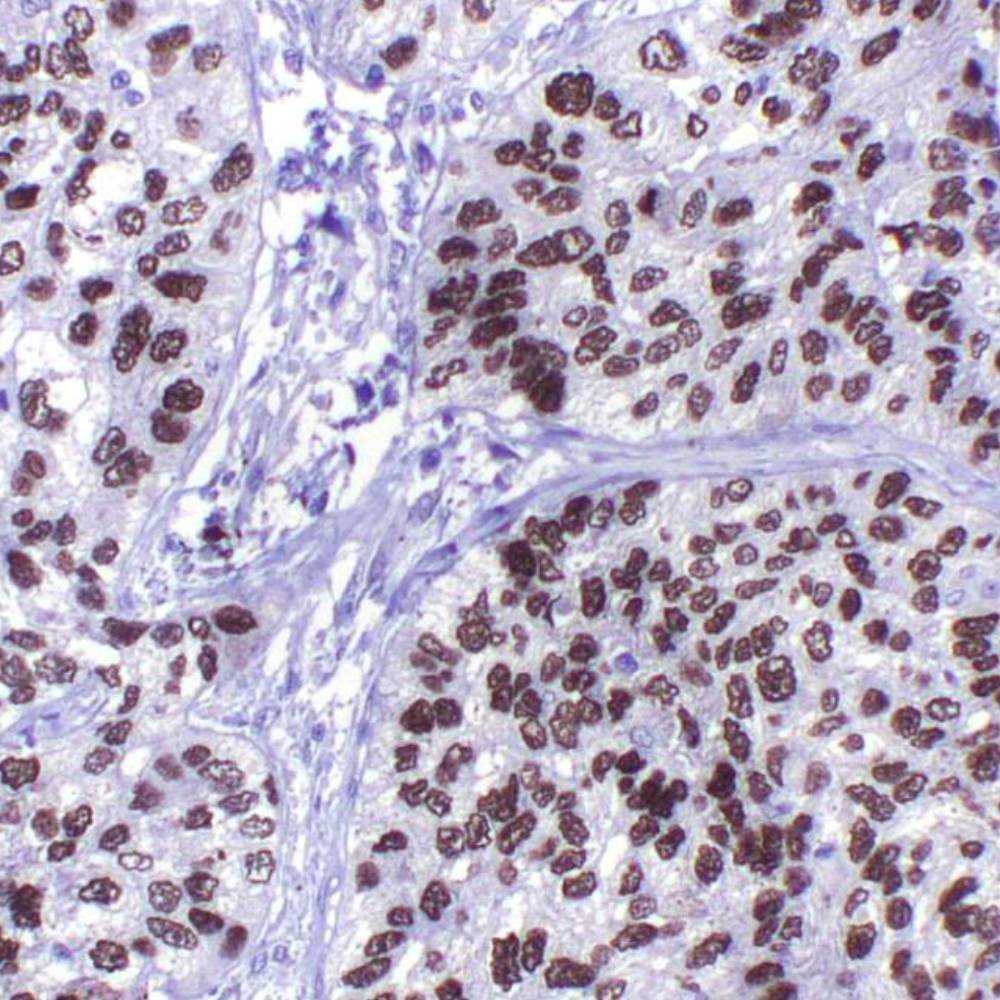

The Ki-67 protein is a nuclear protein doublet, 345-395 kDa, playing a pivotal role in maintaining cell proliferation. In diagnostic histopathology and cell biology, the antibody has proven valuable for the demonstration of the Ki-67 antigen in normal and neoplastic cells, for example in soft-tissue sarcoma, prostatic adenocarcinoma, and breast carcinoma. The Ki-67 has been confirmed as a very powerful single prognostic factor for overall survival, with highly proliferative cases showing a much poorer outcome than tumors with low proliferation. In breast cancer, the proliferative index measured by Ki-67 immunoreactivity has both prognostic and predictive value.